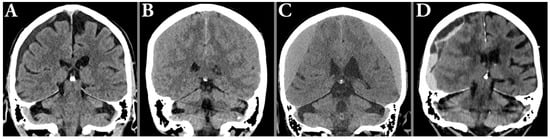

2.8. Hematoma Characterization

2.9. Uni- and Bilateral Hematomas